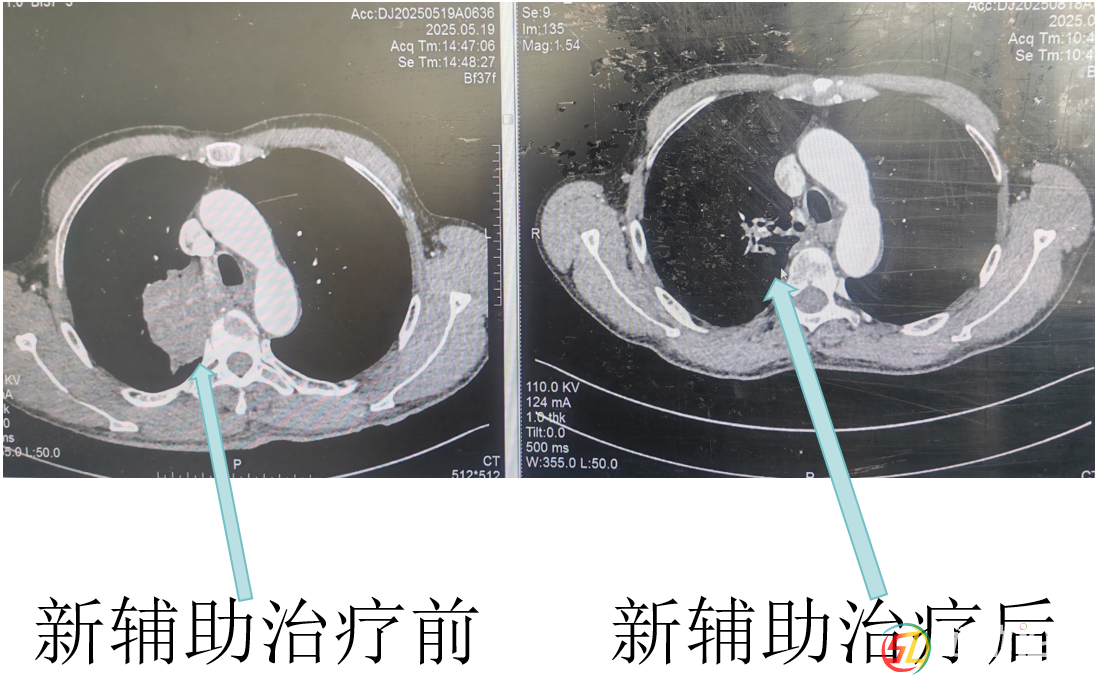

經(jīng)呼吸與危重癥醫(yī)學(xué)科醫(yī)生杜鵑三個周期的藥物治療后,復(fù)查CT顯示羅大爺肺上的腫瘤明顯縮小了!彭均偉判斷,現(xiàn)在手術(shù)有望完整切除腫瘤。就在大家看到希望時,新的問題出現(xiàn)了。羅大爺有幾十年的老慢支和哮喘病史,肺功能檢查結(jié)果很差,根本達不到肺葉切除的手術(shù)標(biāo)準(zhǔn)。而且他三年前還因為心臟病做過冠脈支架手術(shù),長期服用阿司匹林,這又增加了手術(shù)出血風(fēng)險。面對這些困難,彭均偉先為羅大爺制定了詳細的肺功能康復(fù)計劃,經(jīng)過一段時間的精心調(diào)理,羅大爺?shù)姆喂δ芙K于提升到了可以接受手術(shù)的水平。

手術(shù)當(dāng)天,彭均偉醫(yī)師團隊?wèi){借豐富的胸腔鏡手術(shù)經(jīng)驗,先處理好肺部的血管和支氣管,再仔細分離粘連區(qū)域,成功切除了右上肺葉,并清掃了周圍的淋巴結(jié)。術(shù)后病理結(jié)果帶來了更大的驚喜:腫瘤細胞已經(jīng)完全消失,連之前轉(zhuǎn)移的淋巴結(jié)也轉(zhuǎn)為陰性!這意味著羅大爺通過“轉(zhuǎn)化治療+手術(shù)”的新模式,達到了病理學(xué)上的完全緩解。